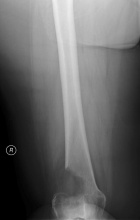

60 year old female with a three month history of mild right knee pain, history of breast cancer, remote smoking history